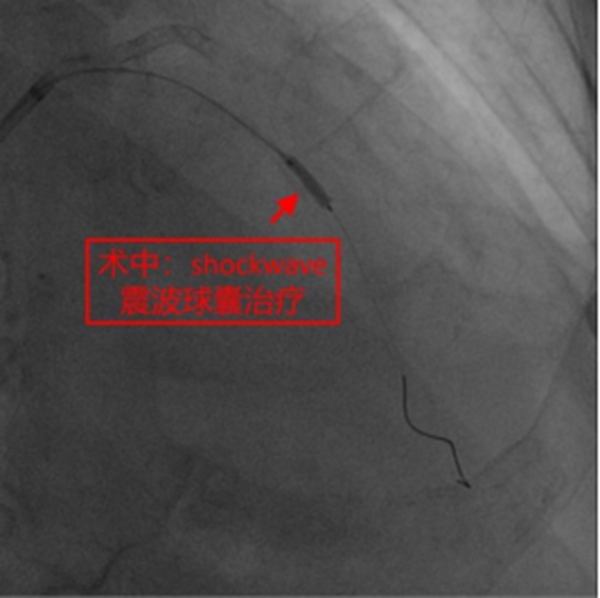

在征得患者及家屬同意,做好充分術(shù)前準備的情況下,冠脈介入團隊在冉擘力主任帶領(lǐng)下,按計劃給患者實施了血管內(nèi)超聲(IVUS)指導下經(jīng)皮冠脈旋磨+Shockwave沖擊波球囊碎裂鈣化斑塊及支架植入術(shù),術(shù)中團隊克服了一系列困難,最終安全順利地完成了全部介入手術(shù)過程,完全碎裂了環(huán)狀鈣化斑塊,效果非常滿意,歷時約1個多小時,手術(shù)成功,病人安返病房。術(shù)后患者胸悶、氣短明顯緩解,對治療效果十分滿意。

而Shockwave沖擊波球囊則是將鈣化斷裂術(shù)+低壓力血管成形術(shù)整合在同一帶有脈沖電極的球囊導管內(nèi),在球囊低壓擴張時向病變提供未聚焦、圓周和脈沖式的機械能以高效和安全地破壞淺表與深層鈣化,也是目前唯一對深層鈣化有治療作用的技術(shù)。沖擊波球囊血管內(nèi)碎石術(shù)是冠狀動脈斑塊旋磨術(shù)的重要補充,而且也為旋磨不成功的病變提供了新的選擇。臨床研究表明,沖擊波球囊治療重度冠脈鈣化病變手術(shù)成功率高、主要不良心血管事件發(fā)生率低、嚴重血管并發(fā)癥極少、管腔殘留狹窄率低、支架擴張良好。